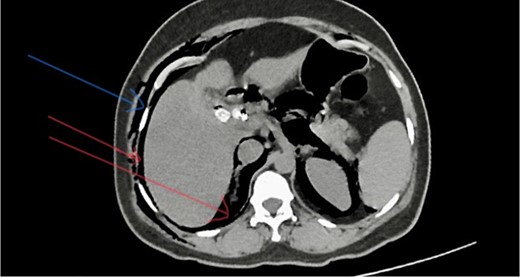

Laboratory investigations showed WBC 13.85 × 106, neutrophils 7.59, Hb 12.8 g/dl, platelet count 287 000 × 106, CRP 6.3, PT/INR 0.85, AST 75, ALT 53, ALP 88, and total bilirubin 12.0 mg/dl. Her ultrasound scan of the abdomen showed multiple common bile duct (CBD) calculi with intrahepatic and CBD dilatation with mild central cholangitis. Contrast-enhanced computed tomography (CECT) of the abdomen showed proximal CBD calculus with mild common hepatic and intra-hepatic duct dilation and gallstone with chronic cholecystitis (Fig. 1).

She has undergone a semi-elective ERCP in a semi-prone position, under sedation with propofol target-controlled infusion. Major papillae identified with side viewing endoscopy. Guidewire was inserted into CBD, and a cholangiogram was done. It showed dilated CBD up to 1.3 cm, mild dilated hepatic ducts, and a large radiolucent area in the distal CBD (around 1.5 cm). Sphincterotomy was done with a sphincterotome, and the ampulla was dilated up to 1.5 cm with a balloon dilator. Then, a balloon retrieval was attempted and failed, probably due to a stone sticking to the CBD wall. Then, a mechanical lithotripter was used to break the stone, but it failed, damaging the instrument. During the procedure, her oxygen saturation dropped to 75–80%, and she developed surgical emphysema in the face, neck, and upper chest region. In addition, she developed abdominal distention as well. Immediately, she underwent CBD stenting with a 12-cm, 10 French Gauge double pigtail biliary stent and changed her position to supine. Then, she was intubated with rapid sequence induction, and a nasogastric tube was inserted and transferred to the surgical intensive care unit. Post-ERCP, non-contrast computed tomography (NCCT) of the abdomen and chest showed extensive pneumo-peritoneum and retroperitoneal gas with subcutaneous emphysema (Figs 2 and 3). There was no evidence of air leakage on NCCT and no clinical features of peritonitis on subsequent days. So she was managed non-surgically with nasogastric tube (NG), nil by mouth, intravenous fluids with intravenous antibiotics. Clear fluid was started after 24 hours slowly via NG.